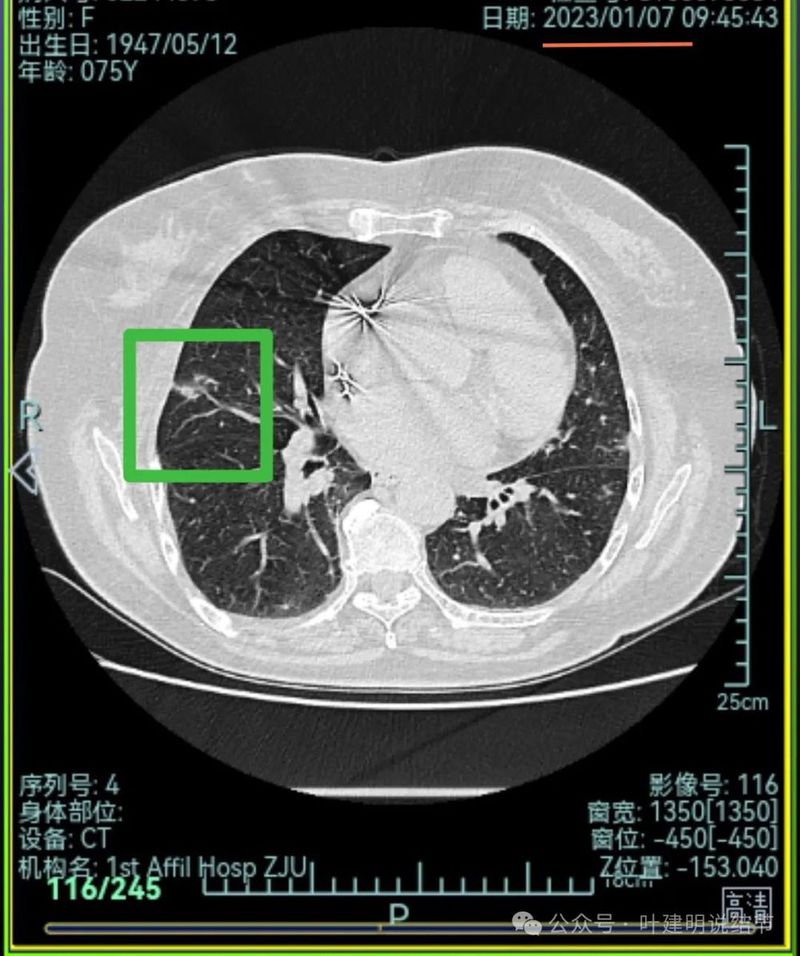

先来看2023年1月时的影像:

右上叶混合密度病灶,有毛刺征,轮廓较清,单次单处看是要考虑恶性的;左上叶磨玻璃结节,轮廓较清,密度较淡,瘤肺边界部分边缘稍不清。

右上叶混合密度结节了,瘤肺边界欠清,周围有晕;左上叶磨玻璃结节,有毛刺征,整体轮廓较清,瘤肺边界略显糊。

右上叶混合密度结节,有分叶征,内部密度杂乱,有毛刺征,灶内有空泡征,单处单灶看也是与恶性较为符合;左上叶两处磨玻璃阴影,轮廓稍糊,边界稍不清,感染稍倾向炎性些。